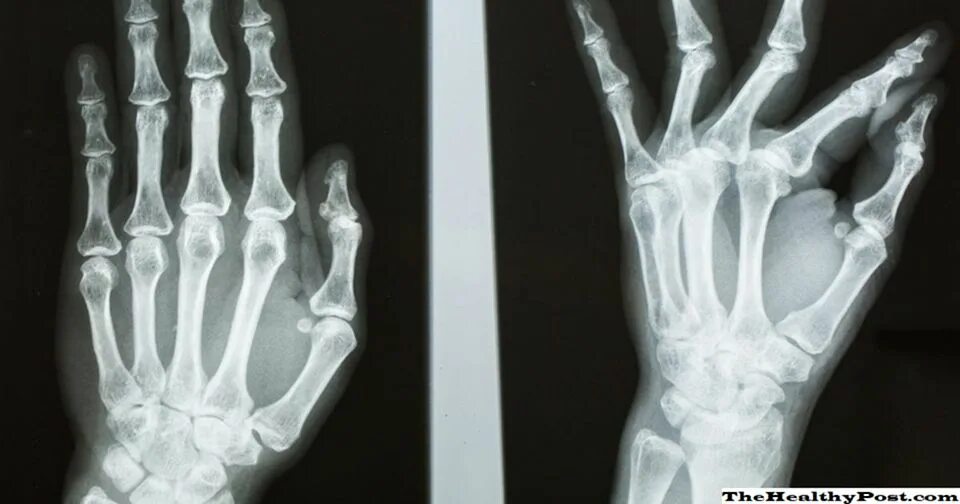

Перелом 3 пястной кости